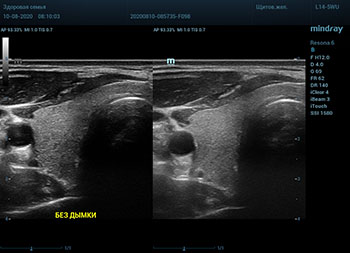

В приборах серии Resona, компании Mindray, появилась новая функция постобработки изображения. Имя ей Dehaze. В переводе на наш родной язык – удаление дымки или рассеивание тумана. Инструмент позволяет корректировать интенсивность тумана или дымки. При этом сохраняется общий контраст и детализация картинки. Dehaze также позволяет проявлять детали снимка в гиперэхогенных зонах и снимать артефакты при чрезмерном усилении.

Готовый снимок или видео петля в формате DICOM несет в себе полное нативное изображение. Прибор позволяет, подобно легендарному фотошопу, удалить лишний «туман». Гиперэхогенный диффузный «засвет» изображения, из-за повышенного общего усиления, часто вредит обследованию. Однако без него некоторые вещи не видны. Показать гипоэхогенные участки и скрыть эхогенную дымку и позволяет Dehaze.

Всё что требуется от доктора – нажать кнопку или повернуть ручку. Мгновенная оптимизация. Мгновенно чистое изображение.